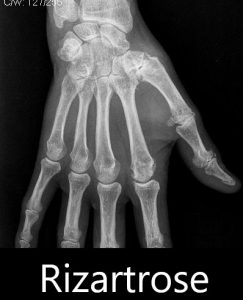

Rizartrose

Rizartrose é o nome dado à artrose da base do polegar.

A artrose é caraterizada, entre outras alterações, por um desgaste da cartilagem articular e formação de osteófitos (os vulgares bicos de papagaio).

A base do polegar é composta por várias articulações, das quais, a mais importante e mais frequentemente atingida pela artrose é a articulação entre o trapézio e o primeiro metacarpiano. O trapézio faz parte dos 8 ossos que compõe o carpo e situa-se entre o escafoide e o referido 1º metacarpiano (metacarpo do polegar).

Com o avançar da artrose surgem osteófitos, tornando a deformidade mais visível.